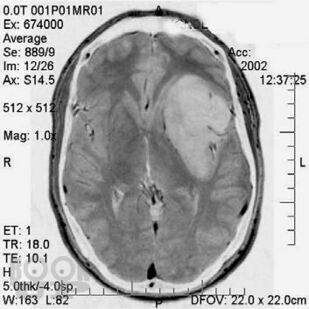

Первичные опухоли головного мозга

Кратко изложены этиология, особенности эпидемиологии, патогенеза, классификация и основные клинические проявления первичных опухолей головного мозга, современные принципы клиники, диагностики и оказания госпитальной помощи больным с данной патологией. Представлены алгоритмы обследования и лечения больных с наиболее часто встречающимися опухолями в зависимости от стадии течения патологического процесса.